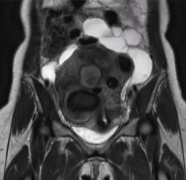

病史 50 岁的女性 由于之前进行过盆腔手术,所以出现了多个增大的子宫肌瘤以及腹膜内囊肿的情况。 已经持续數月遭受嚴重的骨盆疼痛之苦。 药物治疗 盆腔冠状位 T2 加权磁共振成像:多发子宫肌瘤及腹膜内囊肿。 治疗方案选择 由于存在粘连,子宫切除手术无法...